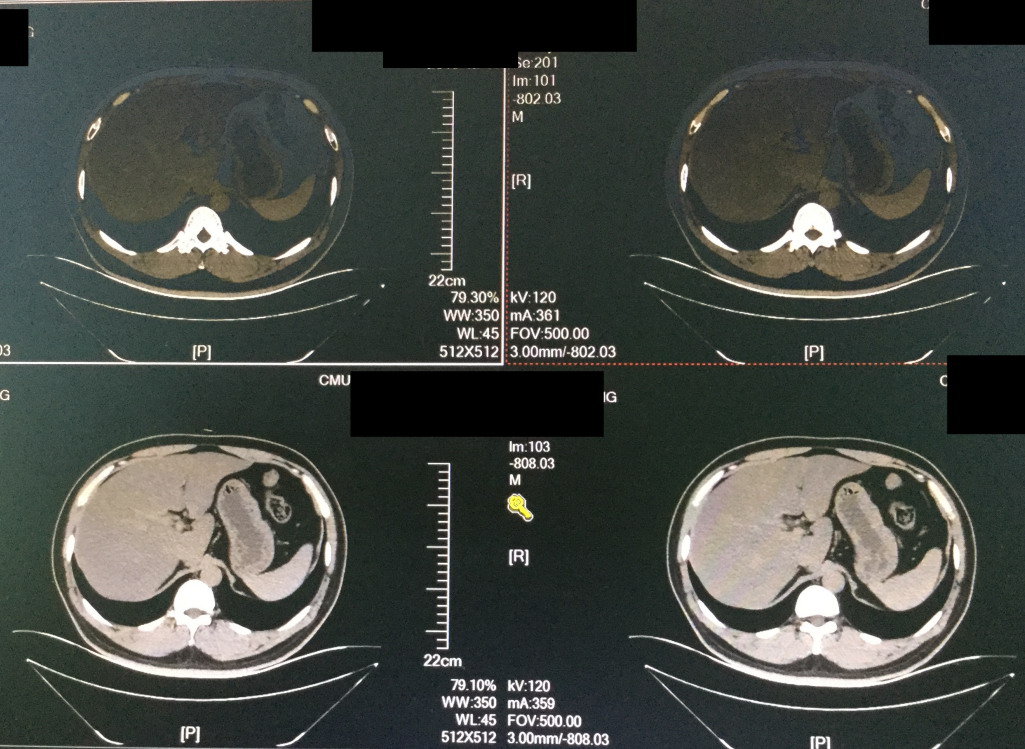

患者就诊主诉持续性上腹痛2日,患者来院后急查血,患者血淀粉酶256u/L,高于正常值200u/L,血脂肪酶1050u/L,高于正常值,CRP4.75mg/L,在正常值0-10mg/L之间。立即给患者禁食禁水,1级护理。平扫上腹,下腹及盆腔后,结果显示胰腺炎,脂肪肝,回盲部、肠系膜根部及直肠系膜内、双侧盆壁内散在稍大淋巴结。